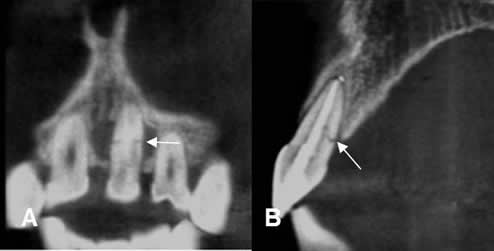

Fig 78. Fractura dental.

A: TAC reconstrucción coronal y B: TAC reconstrucción sagital. Fractura no desplazada y en sentido transverso,

sobre la parte media del incisivo.